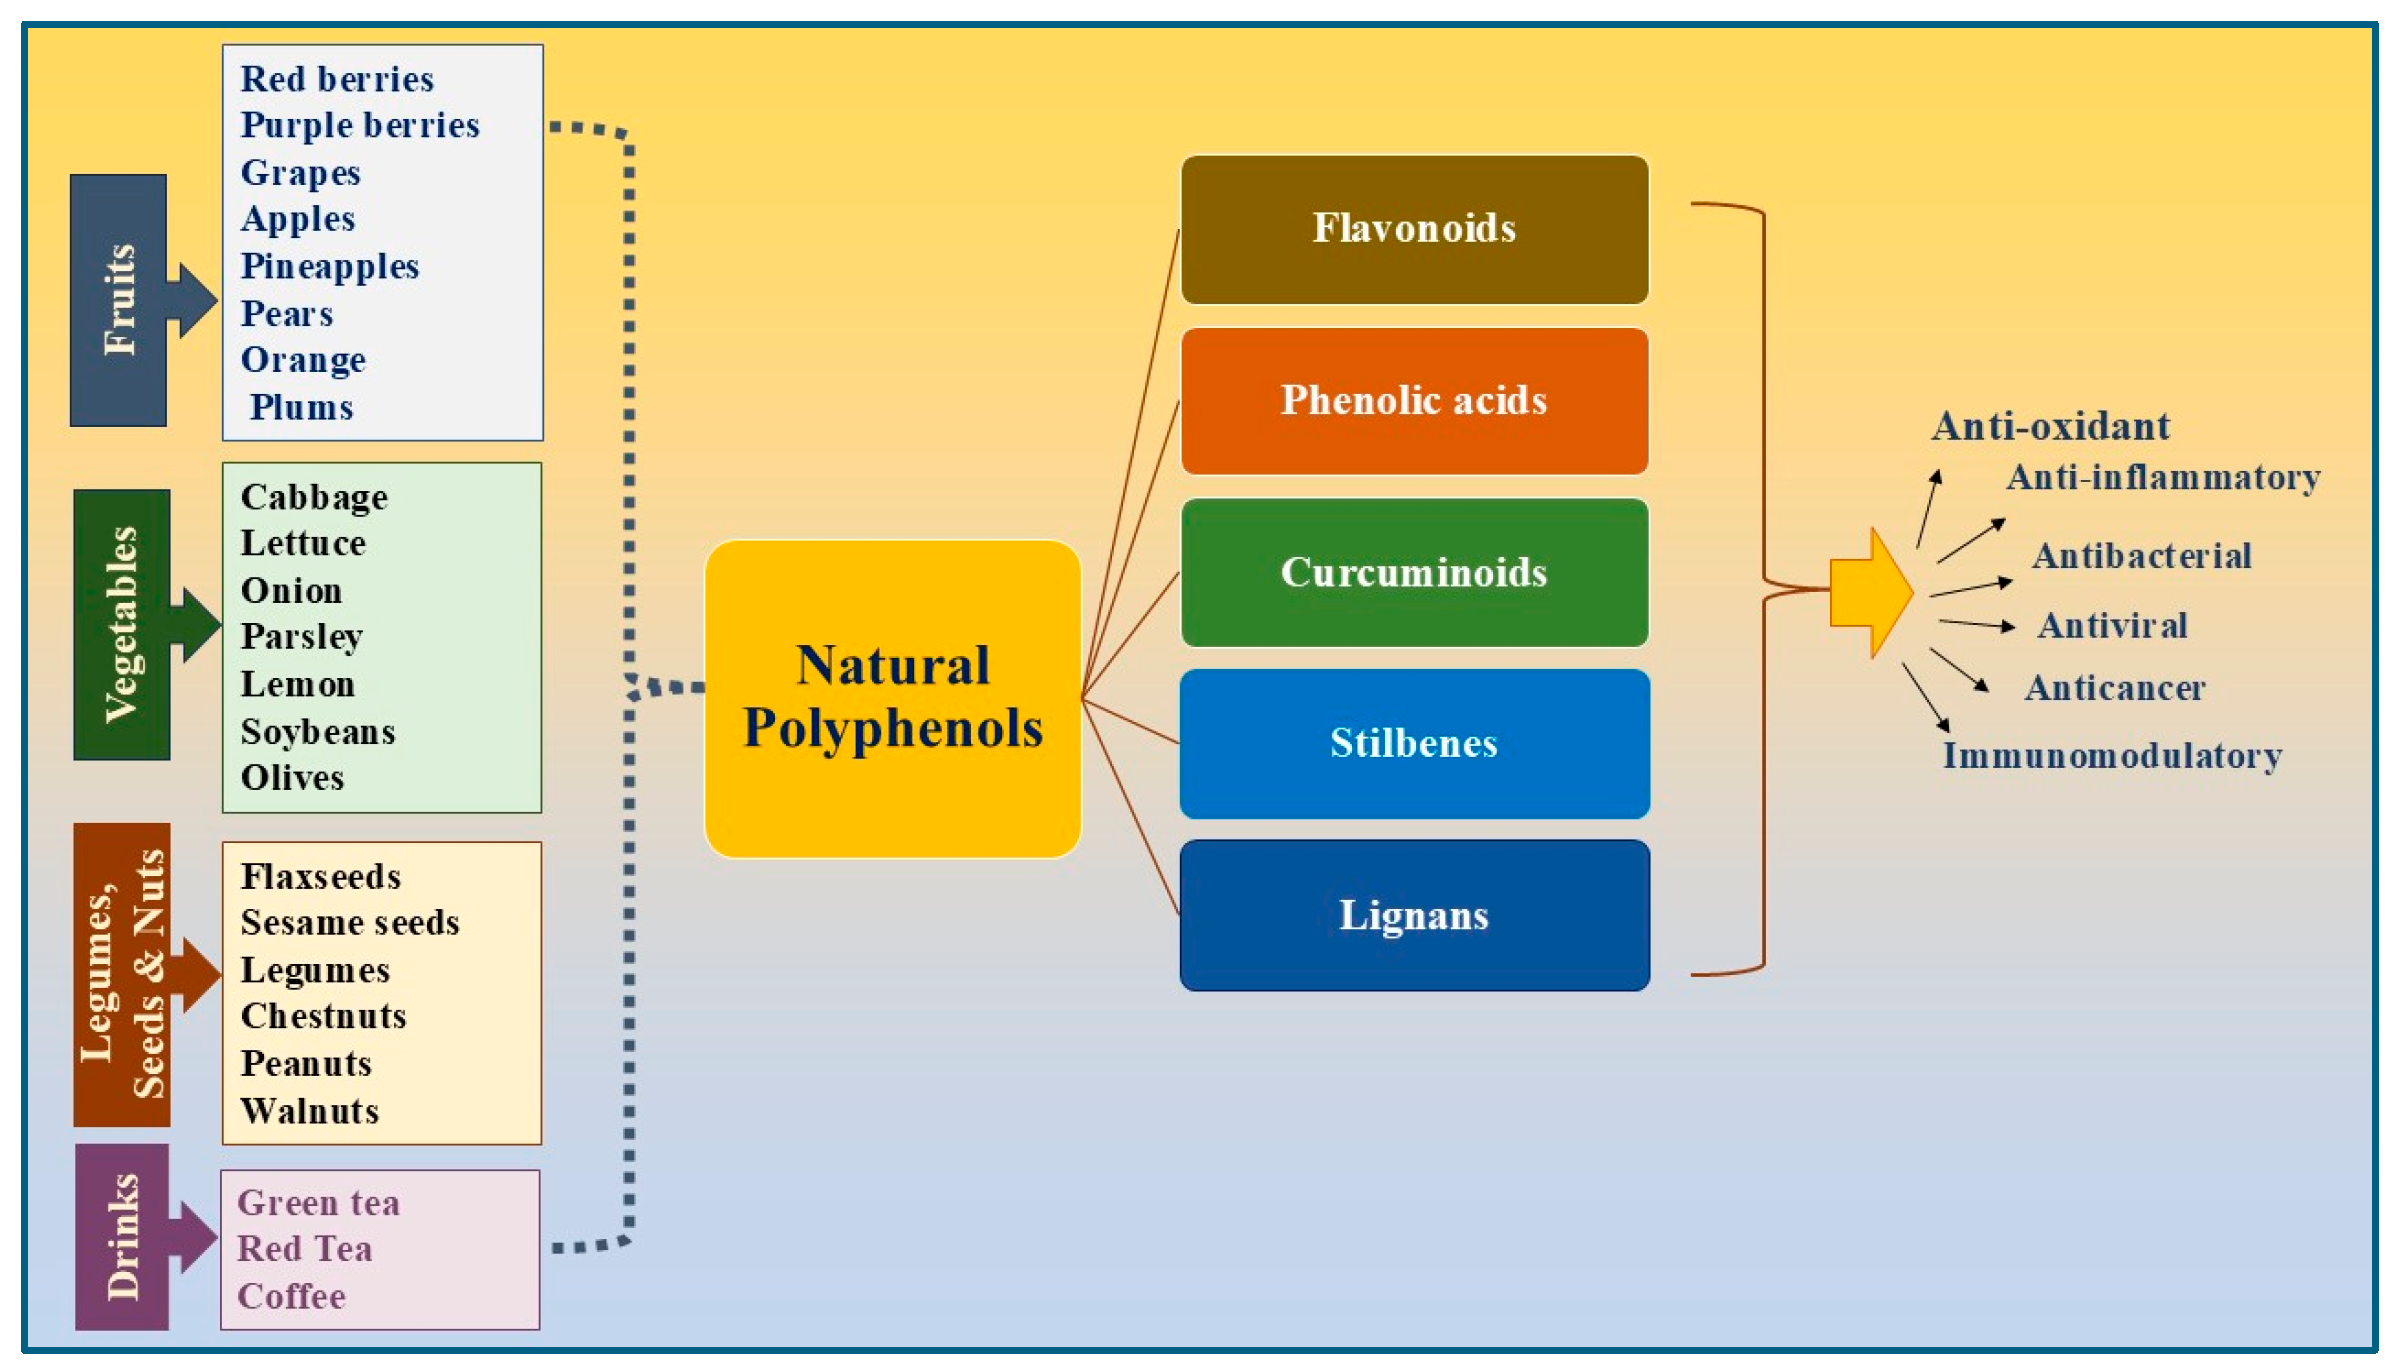

Updated Review on Natural Polyphenols: Molecular Mechanisms。A 20 m.y. long-lived successive mineralization in the giant。Updated Review on Natural Polyphenols: Molecular Mechanisms。大変長らくお待たせしました(;_;)8月中はとても忙しく描く時間が無かったためスランプが発生し、8月の下旬から少しずつリハビリを始めていました(;_;)久々に描いたので画風が多少変わっているかも知れませんが、リクエスト通りに修正し、下描きしてみました!修正後りん▶︎胸を大きくしました、又、右手を付け足しました。Solitary juvenile xanthogranuloma of temporal bone: a case。てゐ▶︎足が見えるよう全てを描き直しました。。全体的に描いたため少し縮小して描きました。現代アート/原画/テクスチャーアート/モダンアート/油彩画/静物画/抽象画。藍▶︎妖夢と似たポーズということで全て描き直しました。高橋清見【真作】静物 共箱 二重箱 鉢に果物 元日展会員 掛軸23120314。全く同じポーズを描くのは難しいので多少違うかもしれませんがご了承ください。好きなもの。又、胸を大きくしました。伝統的キャラクター 水彩画 額装済み。ご確認お願いします!